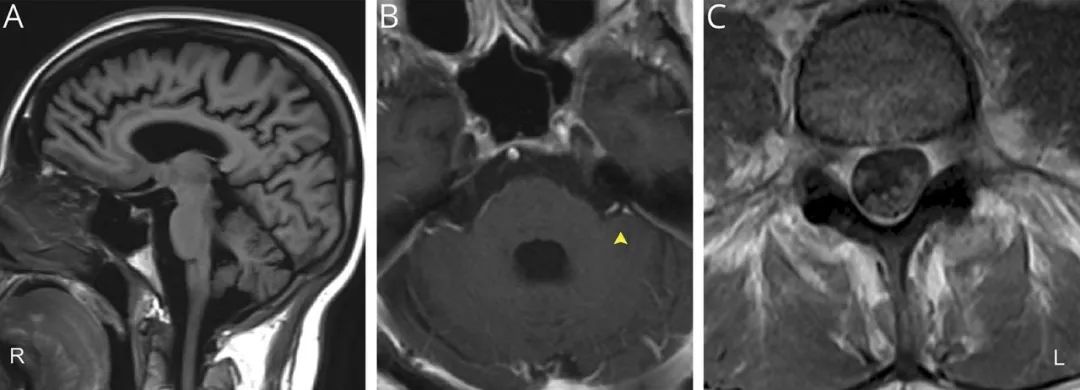

头颅MRI增强显示双侧脑膜增强,累及多条颅神经(III、V和VII / VIII);脊髓MRI显示颈椎和胸椎多个神经根异常增强,马尾神经增强和增粗(图)。CT-PET扫描显示与肉芽肿性疾病有关的多个FDG摄取的淋巴结。经胸超声心动图显示肥厚性心肌病。

图 患者腰椎MRI和头颅MRI平扫及增强结果。(A)最初的头颅MRI平扫显示脑萎缩。(B)后续MRI增强左侧VII和VIII颅神经增强(箭头)。(C)腰椎MRI显示马尾增强。